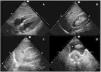

La exploración se realiza rápidamente, en menos de 5minutos, con una sonda sectorial o convexa de baja frecuencia (2,5 a 5MHz) en ventanas ecográficas estandarizadas (pericárdica, flanco derecho, flanco izquierdo y pélvica) (fig. 1). Seguir este orden permite diagnosticar primero el taponamiento cardíaco, la lesión más aguda y potencialmente mortal. Sin embargo, el orden del examen puede cambiar según el mecanismo de la lesión.

Se coloca la sonda en epigastrio, con el indicador hacia el hombro izquierdo y una inclinación de casi 0°. Es importante no confundir la grasa epicárdica con un derrame: la grasa está adherida al corazón y se mueven con él.

Ventana perihepática, flanco derecho o espacio de MorisonSe coloca la sonda, con el indicador hacia la cabeza, entre las líneas medioclavicular y axilar posterior en el espacio intercostal 10°-11°. Se evalúan cuatro espacios: pleural, subfrénico, hepatorrenal (bolsa de Morison) y polo inferior del riñón derecho. Aquí se puede identificar la presencia de líquido libre con mayor sensibilidad.

Ventana periesplénica o flanco izquierdoSe coloca la sonda, con el indicador hacia la cabeza, sobre la línea axilar posterior en el espacio intercostal 8°-9°. Se observan cuatro espacios: pleural, subfrénico, periesplénico y polo inferior del riñón izquierdo. Es una zona de más difícil exploración por la presencia del estómago y por ser el bazo una estructura con peor ventana que el hígado, ya que está asentado más posterior y superiormente.

Ventana pélvica o del espacio de DouglasSe coloca la sonda en una orientación sagital justo por encima de la sínfisis del pubis, en busca de acumulaciones de líquido detrás de la vejiga en los hombres y detrás del útero en las mujeres. La vejiga proporciona la ventana ecográfica; una vejiga vacía no permite la visualización de pequeños volúmenes de líquido libre. Si se ha colocado un catéter vesical, la vejiga puede llenarse parcialmente con suero salino para crear una ventana ecográfica.